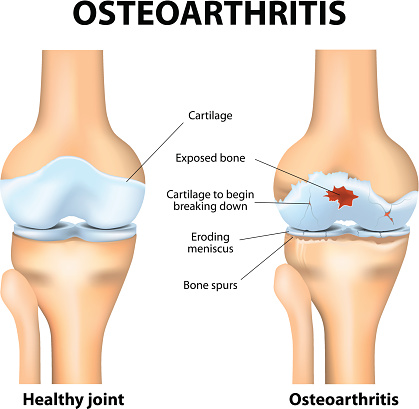

Osteoarthritis treatment based on stem cell discovery helps regenerate tissue, cartilage, and bone: Study

Osteoarthritis treatment based on stem cell discovery helps regenerate tissue, cartilage, and bone, according to research. The stem cells are mixed within human bone marrow stromal cells (MSCs), which were previously hard to distinguish due to similarities in appearance. The researchers isolated the individual MSCs and analyzed their properties, which allowed them to identify which ...click here to read more